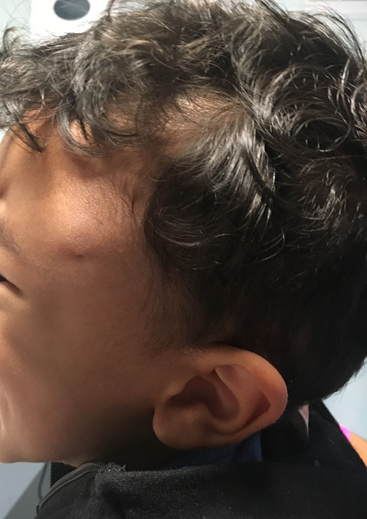

A 29-month-old boy presented to the emergency department with a 48-hour history of left palpebral swelling without inflammatory signs or other associated symptoms. No precipitating factors were identified. The parents reported three previous similar episodes in the last 1.5 years with spontaneous resolution within 48-72 hours. The other episodes were associated with serous drainage. On examination (Figure 1) there was a left palpebral soft swelling with extension to the frontal region. In the middle of the tumefaction there was a one-millimeter orifice, without spontaneous or by expression drainage. A soft tissues ultrasound was performed at the Emergency Department, that revealed a fistulous path from clinically evident dermal lesion with apparently intracranial extension, without signs of local complications. A magnetic resonance imaging (MRI) corroborated the ultrasound findings (Figure 2). In the present case, the patient was discharged with a programed neurosurgery appointment. The boy has maintained regular follow-up in pediatric and neurosurgery consultations, waiting for spontaneous resolution, once there were no major complications in the two-year follow-up period.

Figure 2. MRI image from the lesion.